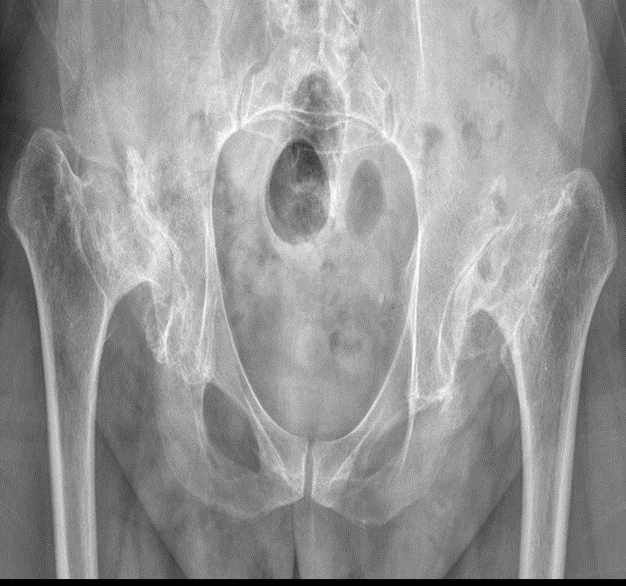

經(jīng)過(guò)前期的網(wǎng)絡(luò)溝通,我們了解了患者的基本病情并進(jìn)行了初步手術(shù)評(píng)估?;颊哂?月9日入住我科。入院后,我科再次進(jìn)行全面評(píng)估與術(shù)前規(guī)劃,并組織了四級(jí)手術(shù)術(shù)前多學(xué)科討論,以確保手術(shù)的安全性。分別于3月13日和28日接受了“右側(cè)全髖及左側(cè)全髖置換術(shù)”。經(jīng)過(guò)1個(gè)月的治療,患者于4月7日順利康復(fù)。 出院之際,患者為表達(dá)感謝,便出現(xiàn)了開(kāi)頭的感人一幕,此次成功實(shí)施的先天性髖關(guān)節(jié)全髖置換手術(shù),彰顯了市公衛(wèi)中心骨外科的雄厚實(shí)力。下一步,骨外科將持續(xù)提升醫(yī)療技術(shù)水平和服務(wù)水平,為廣大患者提供更優(yōu)質(zhì)的醫(yī)療服務(wù)。